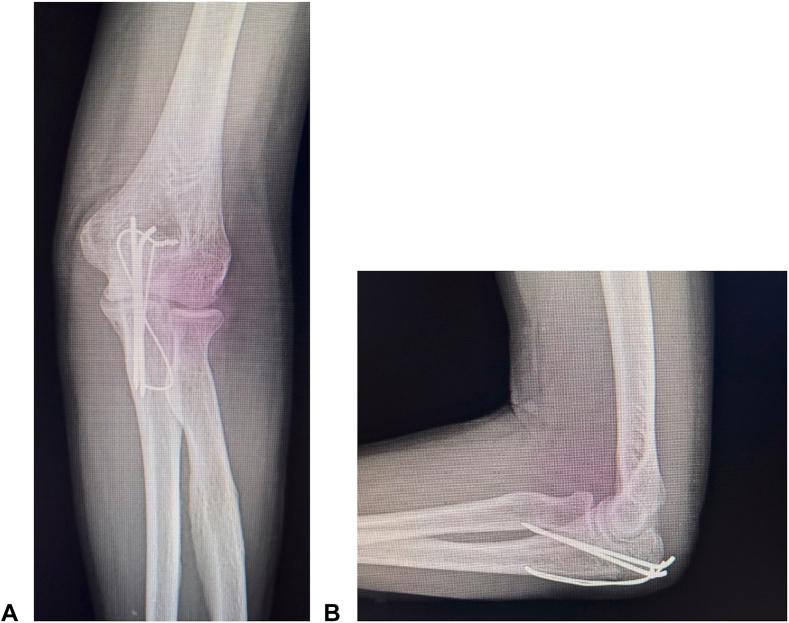

A total of 40 patients (17 men and 23 women; mean age: 64.0 ± 19.0 years) who underwent surgery for displaced olecranon fractures between January 2018 and December 2021 were included and divided into three groups based on the surgical method used (group A, conventional TBW; group B, TBW with penetrating technique; and group C, double-bending technique). Thirteen patients were assigned to group A, 17 to group B, and 10 to group C, including 2 Mayo type IB, 30 Mayo type IIA, and 8 Mayo type IIB fractures. Postoperative outcomes (elbow extension and flexion arc) and complications, such as backing out of the Kirschner wire (K-wire), were retrospectively evaluated.

No significant difference was found in the general characteristics of the patients and fracture type among the three groups. The mean elbow extension arc values were 6.2°, 10.9°, and 0° in groups A, B, and C, respectively; it was significantly better in group C than in group B ( = .001). The rates of backing out of the K-wire were 84.6% (11/13) in group A, 41.2% (7/17) in group B, and 0% (0/10) in group C; the rate was significantly lower in group C than in group A ( < .001).

The double-bending technique may be the best procedure for preventing the backing out of the K-wire and postoperative complications, such as range of motion restriction, for treating olecranon fractures that are treatable by TBW.